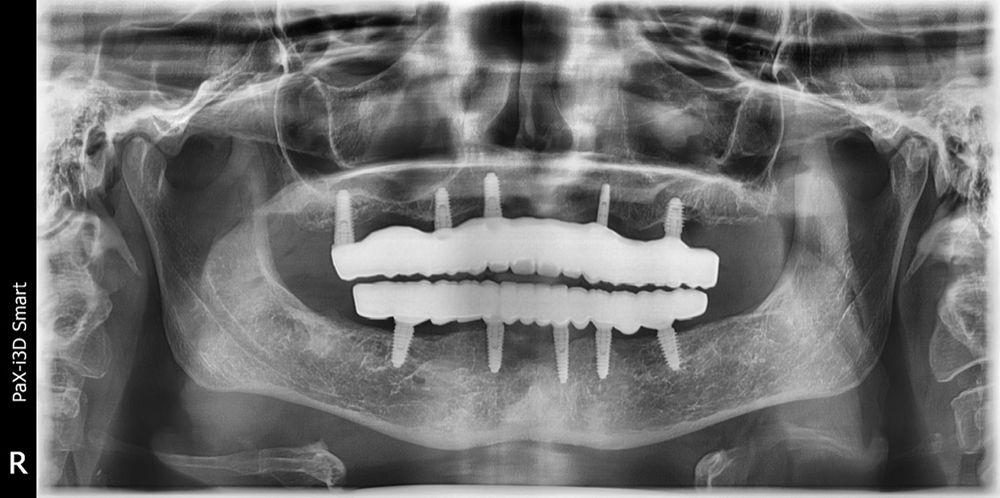

The case is restored and the patient is very happy, but Dr Gupta is not. Every time he sees her name on the schedule for a recall exam, prophy, and implant maintenance, he is nervous that 1 of those upper implants is going to fail or that threads are going show (Figure 3).